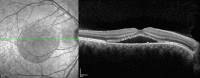

Central Serous Chorioretinopathy: Pathogenesis and Management

Central serous chorioretinopathy (CSC) is a common retina disease and has a relative high recurrence rate, etiology, and pathogenesis of which remains largely ambiguous. The effects on the retina are usually self-limited, although some people are left with permanent vision loss due to progressive and irreversible photoreceptor damage or retinal pigment epithelium atrophy. There have been a number of interventions used in CSC, including, but not limited to, laser treatment, photodynamic therapy (PDT), intravitreal injection of anti-vascular endothelial growth factor agents, and subthreshold lasers. It is not clear whether there is a clinically important benefit to treating acute CSC, which often resolves spontaneously as part of its natural history. Of the interventions studied to date, PDT and micropulse laser treatment appear the most promising. .